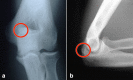

Figures